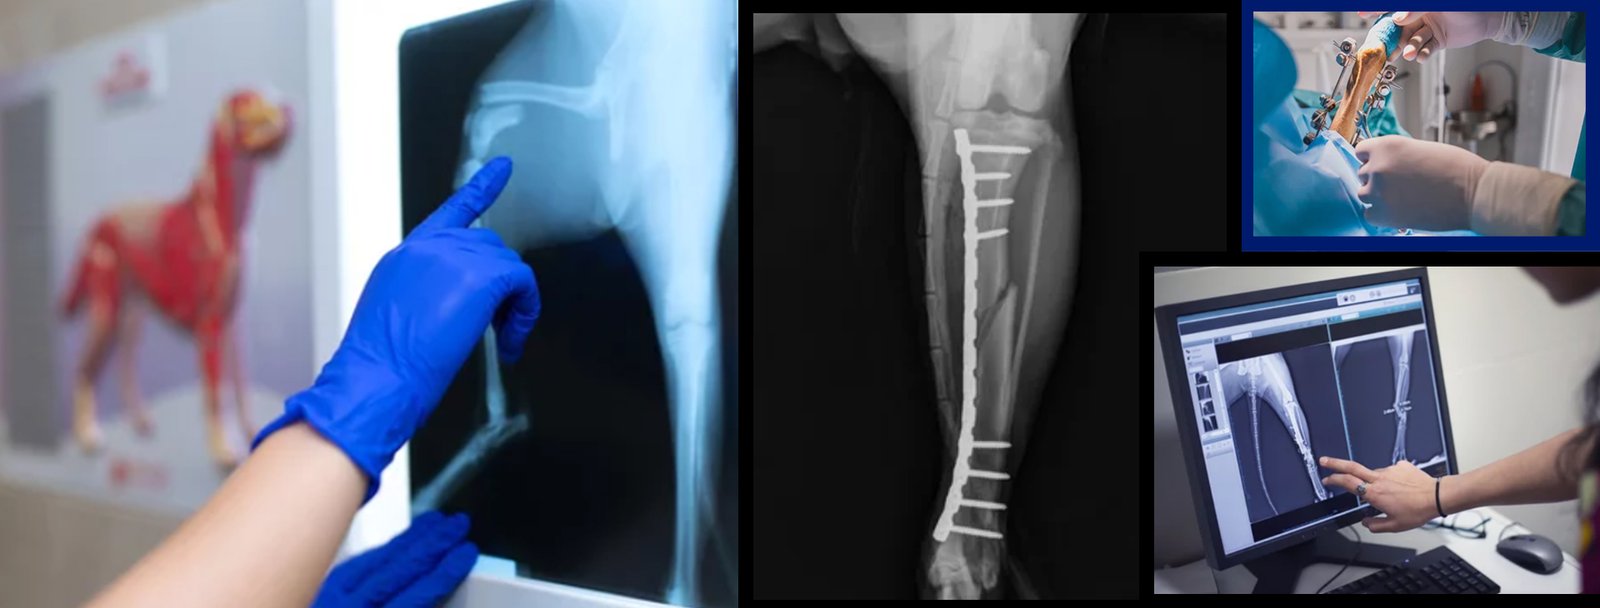

Our team of veterinary specialists encompasses extensive experience in almost all areas of animal surgeries, including advanced soft tissue and orthopedic surgeries, and neurosurgery. By utilizing advanced diagnostic and therapeutic equipment, our specialists work together to deliver individualized care for your pet.